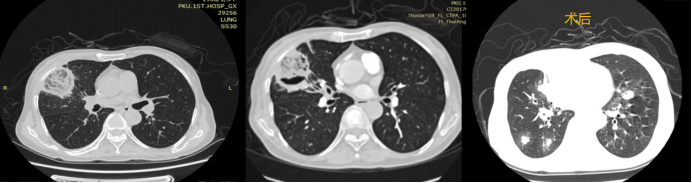

病例4:一例白血病合并毛霉感染患者。影像学检查可见胸膜下反晕征及空气新月征(图4)。该患者经内科治疗病情好转后,接受了手术切除治疗,但术后2周出现感染再次播散,最终不幸死亡。此病例表明,即使采用内科治疗联合手术切除的传统方案,肺毛霉病仍可能因感染播散导致不良结局。

图片

图4  病例4手术前后胸部CT